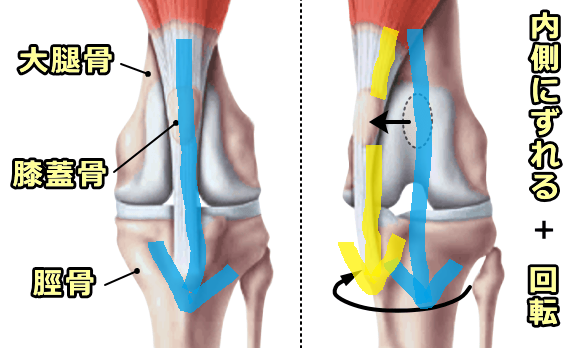

膝関節は①大腿部(太もも)の筋肉、②膝蓋靭帯、③膝蓋骨、④脛骨粗面(膝蓋靱帯の脛骨への付着部)の4つが大腿骨の中心線上に一列に整列することにより、膝関節曲げ伸ばしがスムーズに行えます。

膝蓋骨脱臼がある子の中には、もともとの足の構造として脛骨粗面が内側にあることにより、この4つの配列が内側に引っ張られ、結果として膝蓋骨が内方に脱臼しやすくなっている子がいます。

これにより4つの構造が大腿骨の中心線上に再整列され、脱臼を整復することができます。